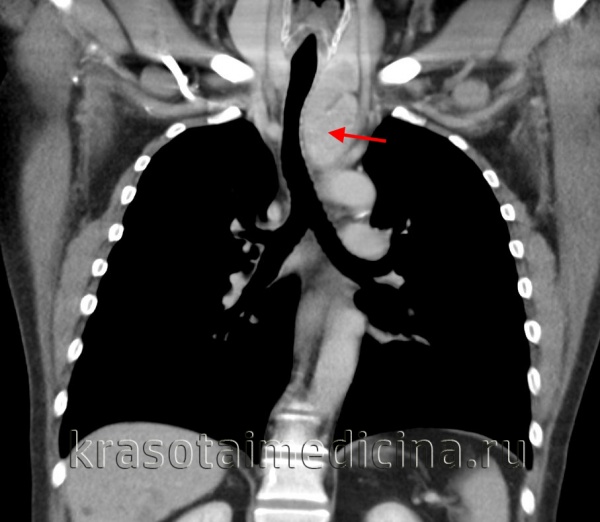

(а) У этого же пациента при КТ с контрастным усилением в средостении определяется объемное образование жировой плотности с криволинейными толстыми мягкотканными перегородками и узелками. При наличии перегородок толщиной более 2 мм и мягкотканных узелков следует заподозрить скорее липосаркому, а не липому.

(б) У этого же пациента при КТ с контрастным усилением на реконструкции в коронарной плоскости визуализируются распространение липосаркомы в заглоточное пространство и циркулярный охват дуги аорты и крупных сосудов.